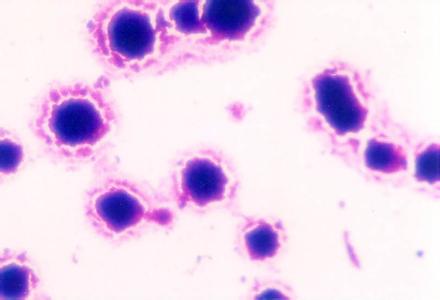

支原体、衣原体是引起泌尿生殖道感染的病原菌。感染后主要引起白带颜色、气味、形状和量的异常。支原体和衣原体可通过性生活相互感染。若病菌体上行感染 盆腔,可导致输卵管阻塞;若病菌感染 泌尿系统,则可引起膀胱炎、肾盂肾炎等。也可感染上皮细胞引起细胞损伤或粘附于精子表面,从而阻止精子运动。成为支原体感染引起不育不孕的原因之一。

支原体衣原体的症状潜伏期为1-3周,典型的急性期症状与其他非淋病性生殖泌尿系统感染相似,表现为尿道刺痛,不同程度的尿急及尿频、排尿刺痛,特别是当尿液较为浓缩的时候明显。尿道口轻度红肿,分泌物稀薄,量少,为浆液性或脓性,多需用力挤压尿道才见分泌物溢出。

泌尿生殖道感染支原体、衣原体后,引起的疾病男性为非淋菌性尿道炎,女性主要为非淋菌泌尿生殖道炎。男性表现为尿道刺痒、烧灼感和排尿困难,少数有尿频。尿道口轻度红肿,分泌物稀薄,部分病人无症状。